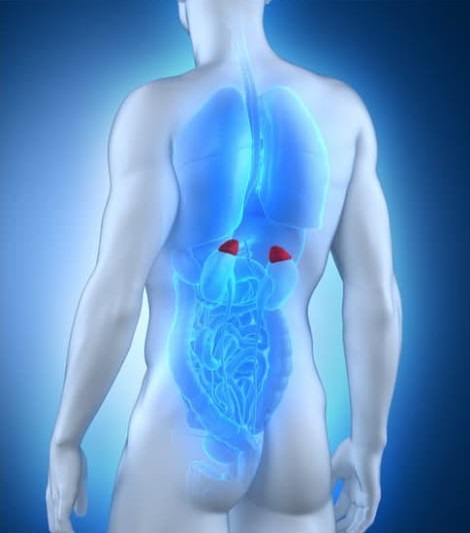

Τα επινεφρίδια είναι δύο μικροί ενδοκρινείς αδένες που εντοπίζονται στο πίσω μέρος της κοιλίας και επάνω από το κάθε νεφρό. Έχουν σύνθετο ρόλο επειδή παράγουν και εκκρίνουν ορμόνες οι οποίες επηρεάζουν σημαντικές λειτουργίες του οργανισμού όπως η αλδοστερόνη, η κορτιζόλη, η αδρεναλίνη. Με αυτό τον τρόπο τα επινεφρίδια ρυθμίζουν τον ανθρώπινο μεταβολισμό, την καρδιακή λειτουργία, την αρτηριακή πίεση, και την αντίδραση του οργανισμού στο stress και τη φλεγμονή, αναφέρει ο κ. Αριστοτέλης Κεχαγιάς, MD PhD FACS, Γενικός Χειρουργός, Προηγμένη Λαπαροσκοπική Χειρουργική, Metropolitan General, τ. Διευθυντής Ελάχιστα Επεμβατικής Χειρουργικής Ενδοκρινών Αδένων Πανεπιστημιακού Νοσοκομείου Τάμπερε, Φινλανδία.

Τα επινεφρίδια βρίσκονται στο πίσω μέρος του οπίσθιου διαμερίσματος της άνω κοιλίας (οπισθοπεριτόναιο) επάνω από τους νεφρούς, στην ανατομική περιοχή της μέσης. Τα υπόλοιπα όργανα της άνω κοιλίας βρίσκονται στο πρόσθιο διαμέρισμα της κοιλιάς (περιτοναϊκή κοιλότητα), δηλαδή μπροστά από το επινεφρίδιο θέτοντας περιορισμούς στην κλασική λαπαροσκοπική διακοιλιακή επινεφριδεκτομή. Κατά την κλασική λαπαροσκοπική επέμβαση απαιτούνται 4-5 τομές στο δέρμα της κοιλιάς και ακολουθεί ευρεία χειρουργική κινητοποίηση και μετακίνηση πολλών οργάνων της περιτοναϊκής κοιλότητας (παχύ έντερο, ήπαρ, σπλήνας, στόμαχος, αλλά και το πάγκρεας) προκειμένου ο χειρουργός να προχωρήσει στο οπισθοπεριτόναιο όπου εντοπίζεται το επινεφρίδιο. Δηλαδή η τεχνική αυτή αναγκάζει τον χειρουργό να ξεκινήσει την επέμβαση από μία ανατομική περιοχή που βρίσκεται μακριά από το επινεφρίδιο και άσκοπα να κινητοποιήσει άλλα όργανα ώστε να φθάσει σε αυτό.